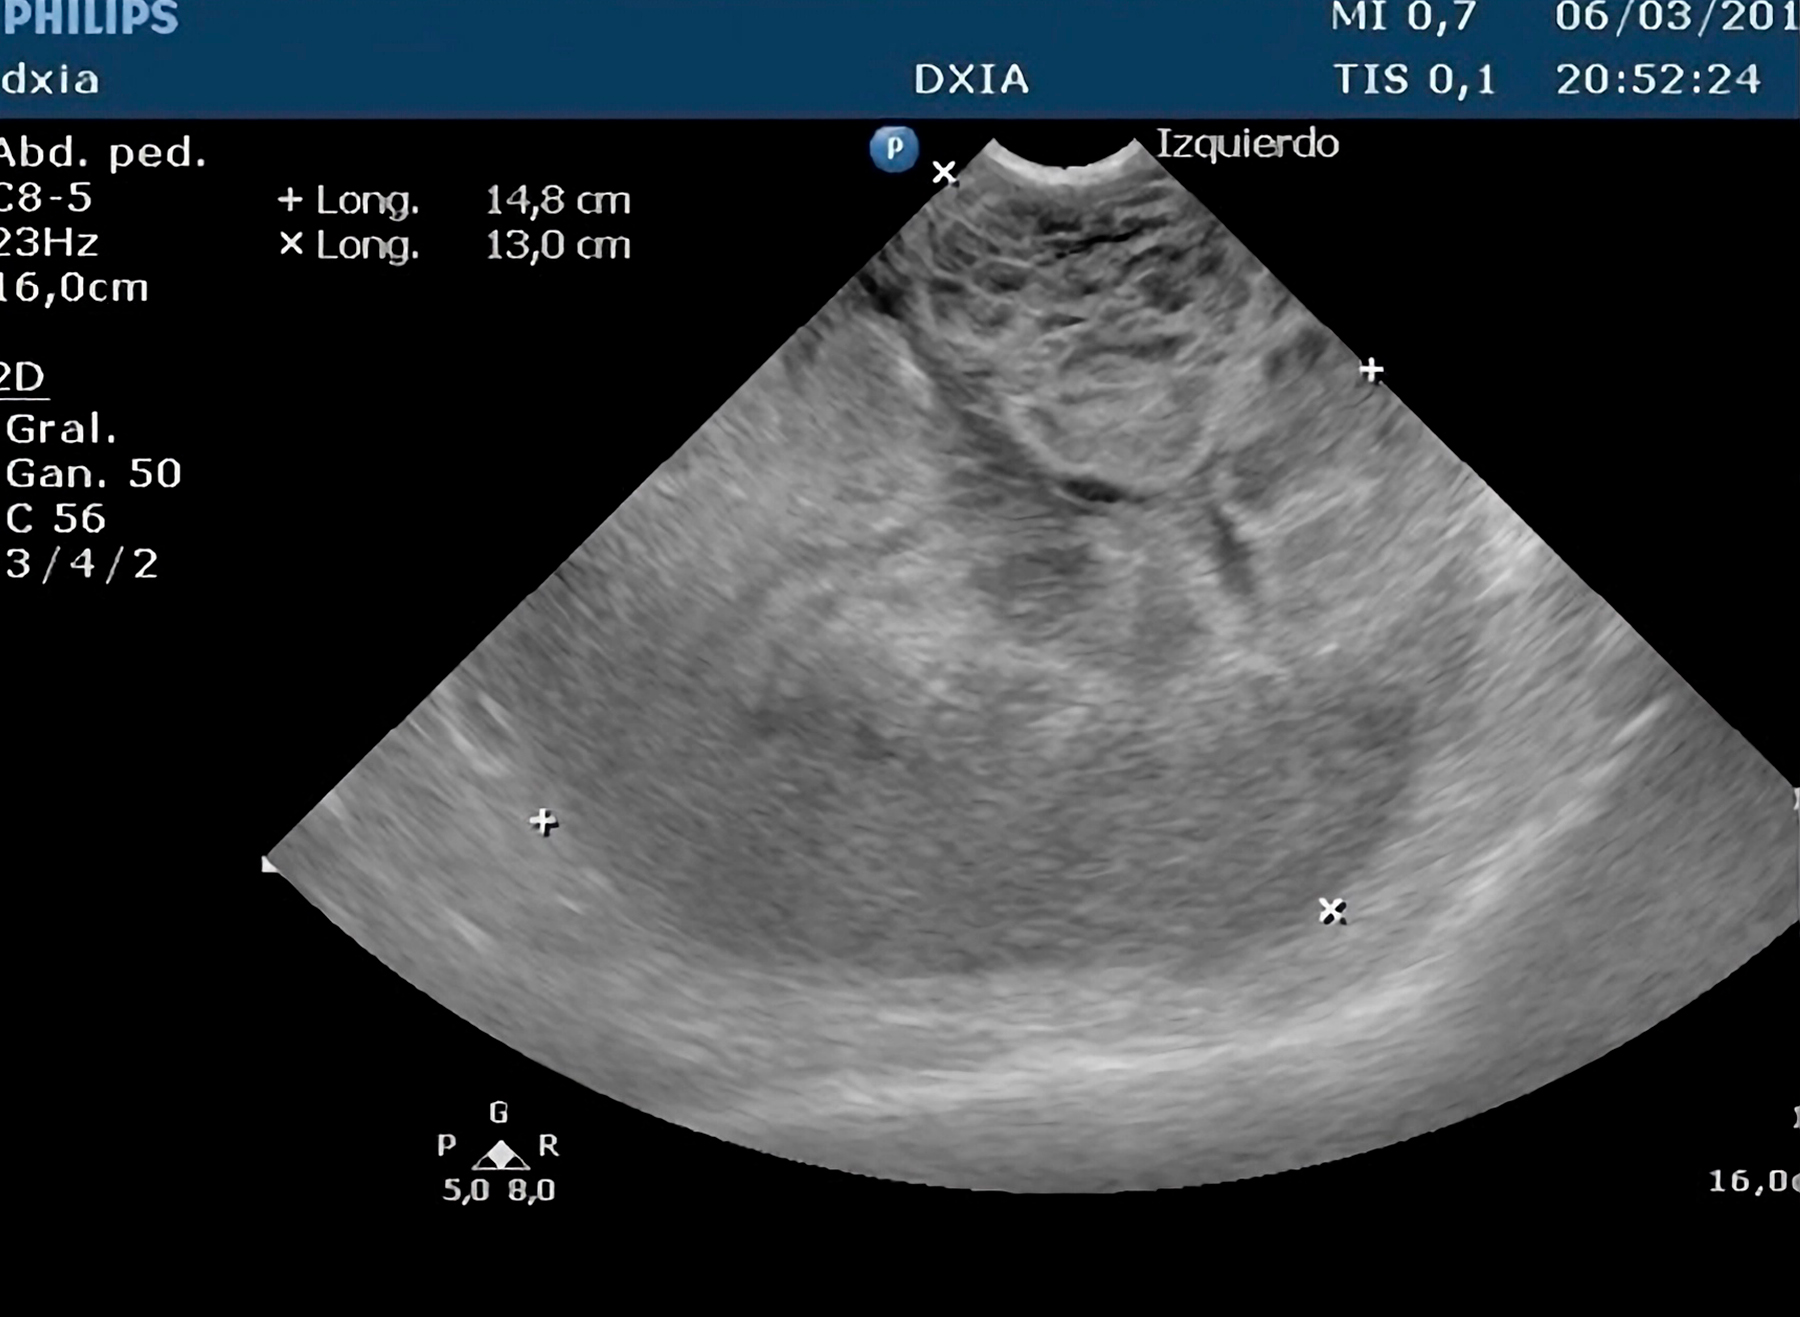

Hallazgos Ecográficos:

Se evidenció interrupción de la continuidad de la cápsula esplénica y una formación heterogénea con efecto masa.